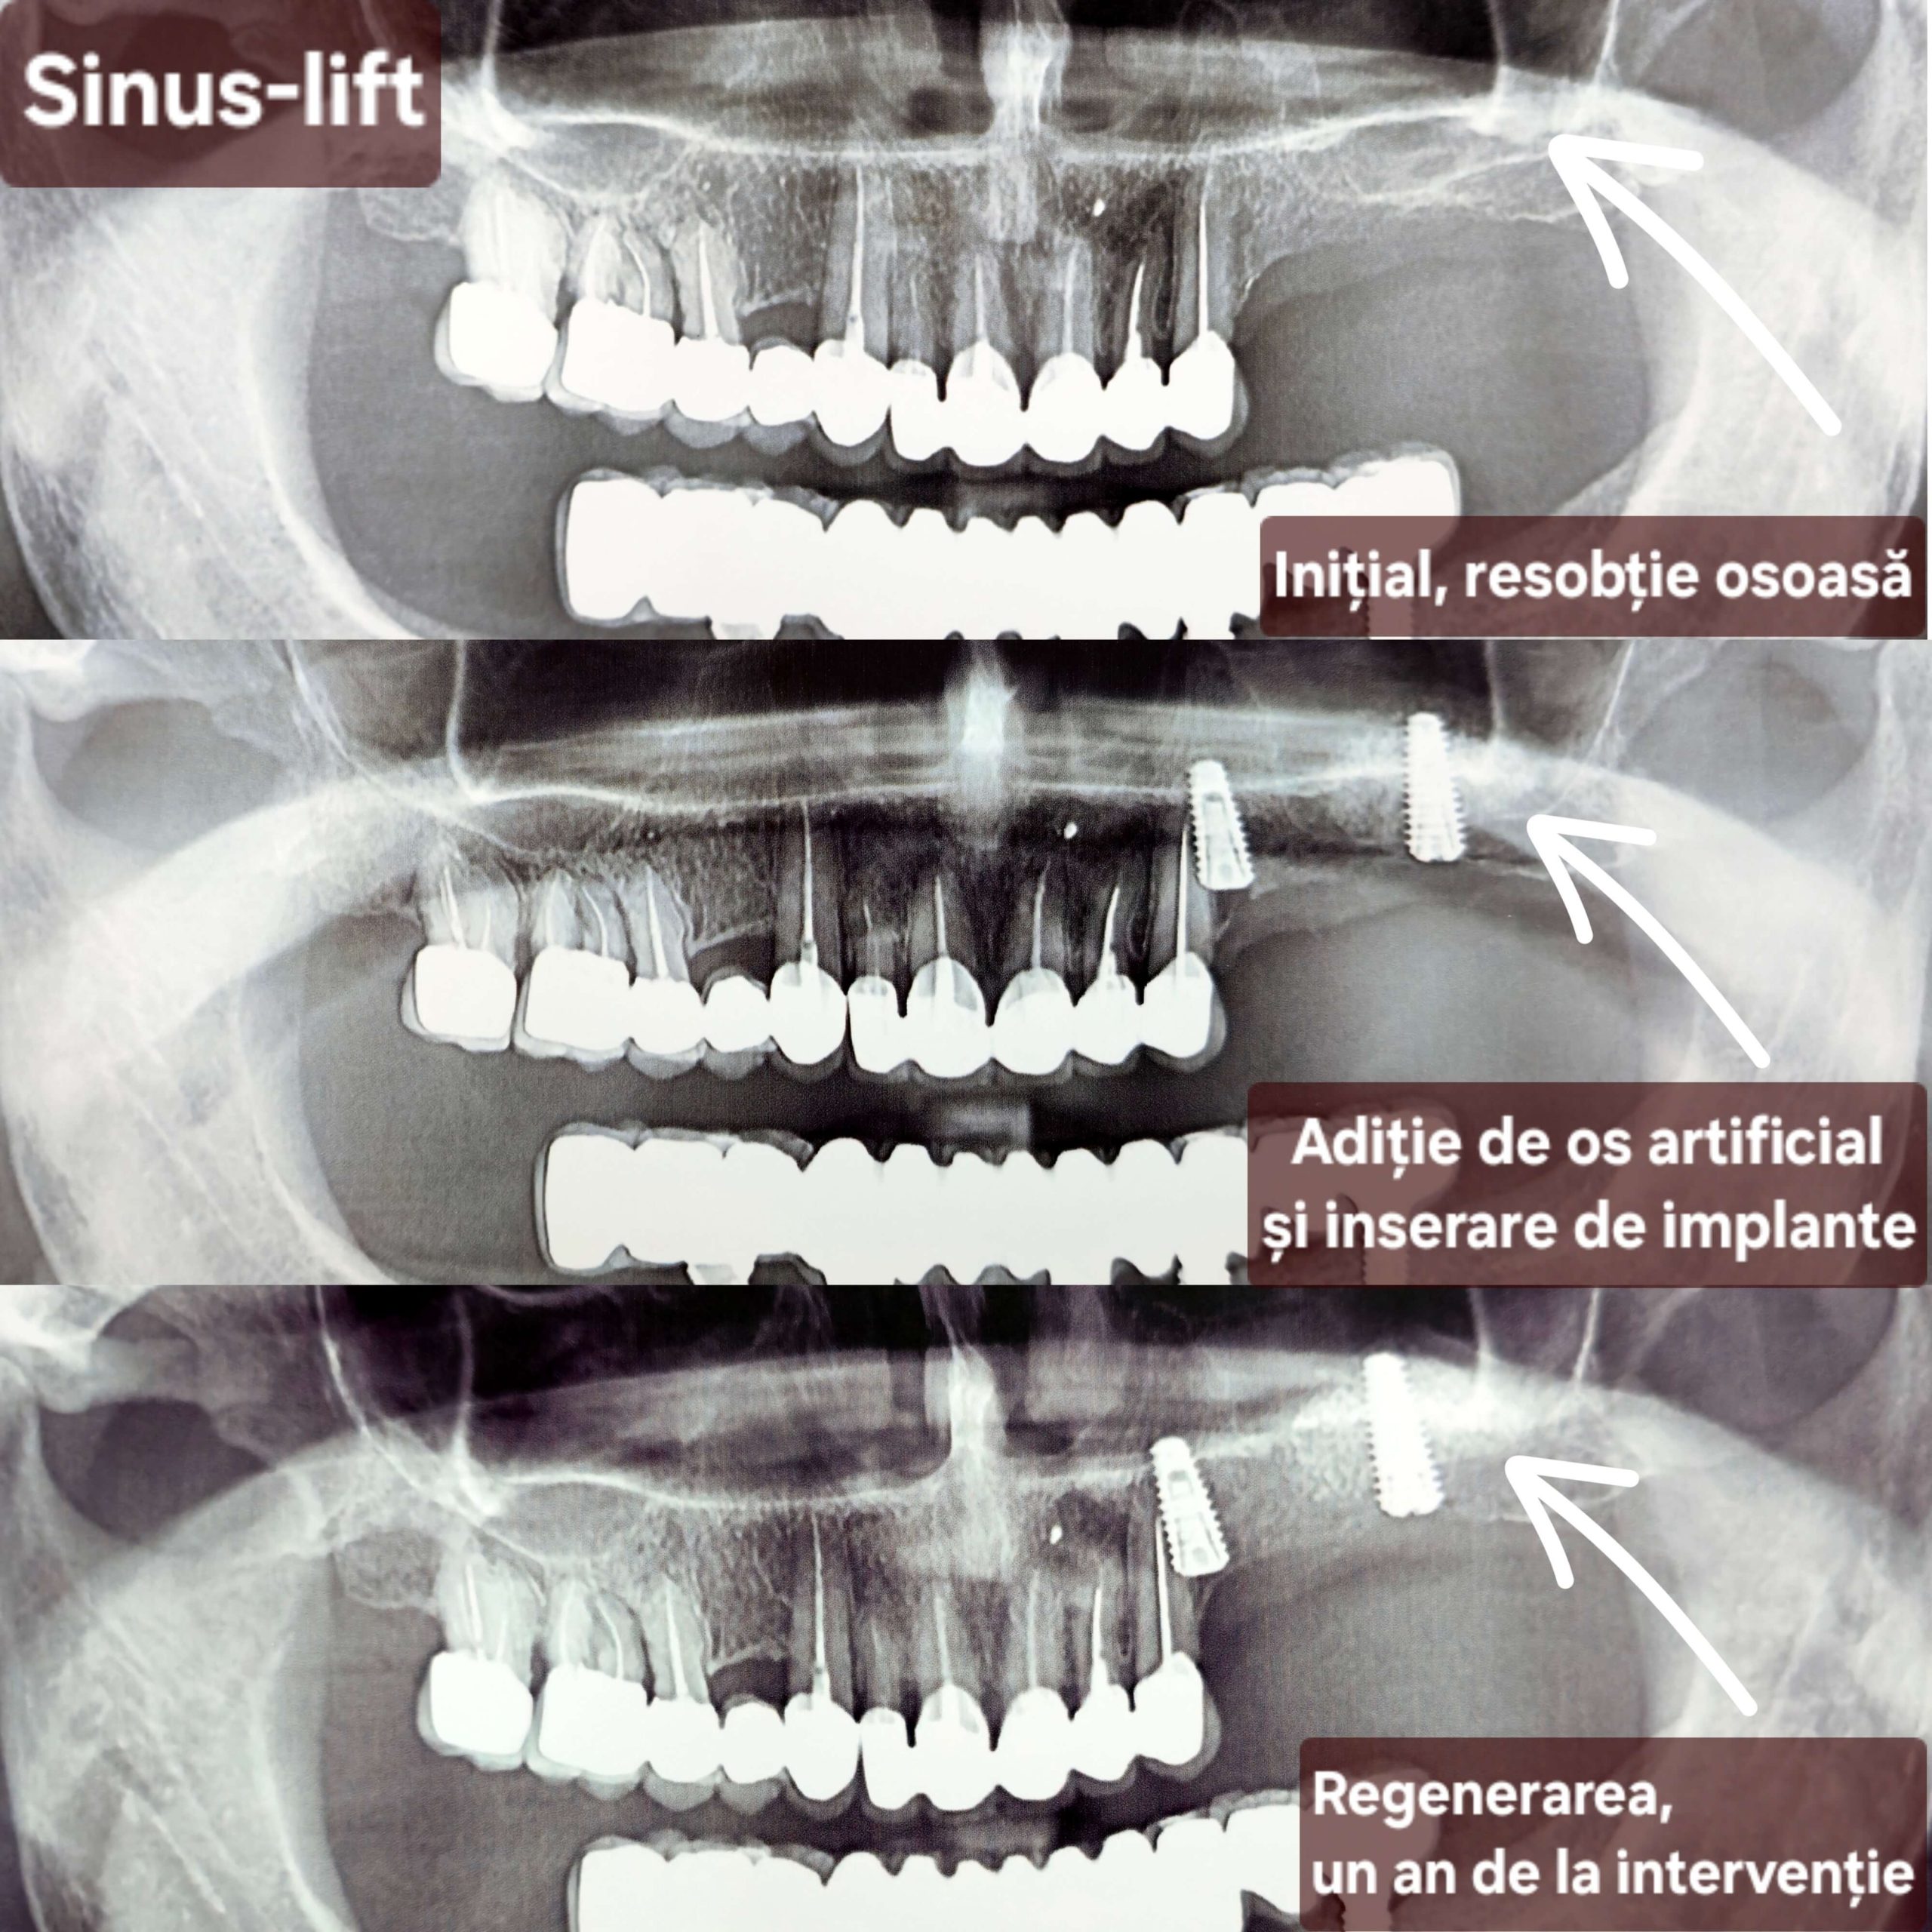

Cea mai răspândită intervenție de augmentare osoasă în stomatologie este operația de sinus lift (ridicarea sinusului) – o procedură chirurgicală de adiție osoasă realizată la maxilarul superior pentru a crește volumul osos necesar inserării implanturilor dentare. Prin ridicarea membranei sinusale și introducerea unui material de grefare, se creează o bază solidă, fiind necesară când sinusurile sunt prea coborâte sau osul este prea subțire. Scopul acestei proceduri este crearea unui suport stabil pentru implanturi dentare în zona laterală superioară (molari/premolari). Procedura de adiție osoasă se efectuează sub anestezie locală. Vindecarea durează de obicei între 4 și 6 luni.

Implantarea și ridicarea sinusurilor permit restabilirea zâmbetului estetic chiar și în cazurile extrem de dificile, adică și în situațiile când pacientul se adresează tardiv. Înainte de apariția acestei tehnici, unii pacienți trebuiau să se mulțumească doar cu proteze și punți mobilizabile. Odată apărută posibilitatea creșterii osoase, contraindicațiile pentru instalarea implantelor au fost considerabil reduse.